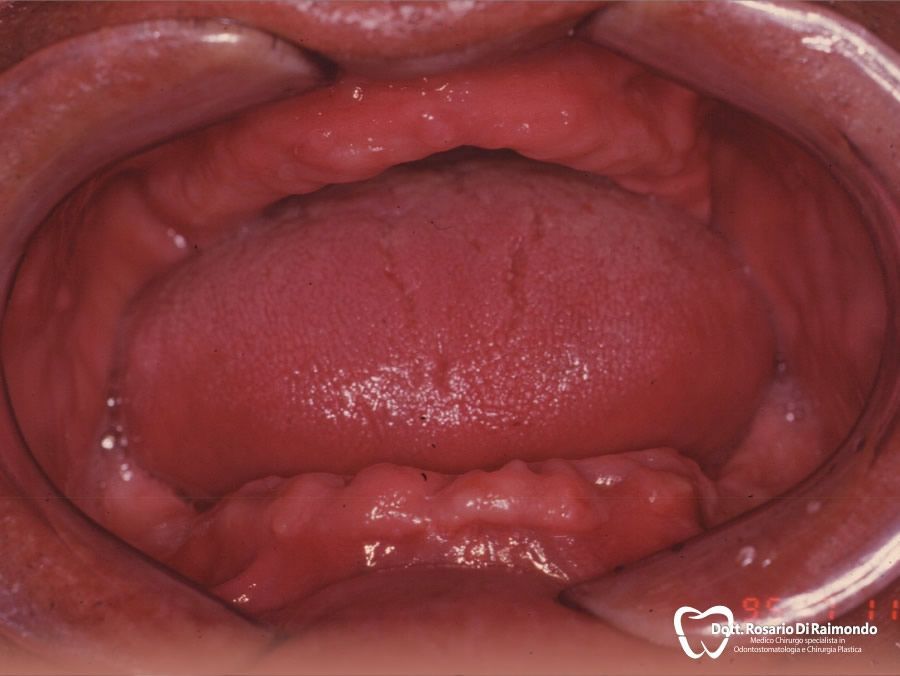

Casi Trattati

Di seguito riportiamo alcune fotografie di casi di Implantologia già trattati.